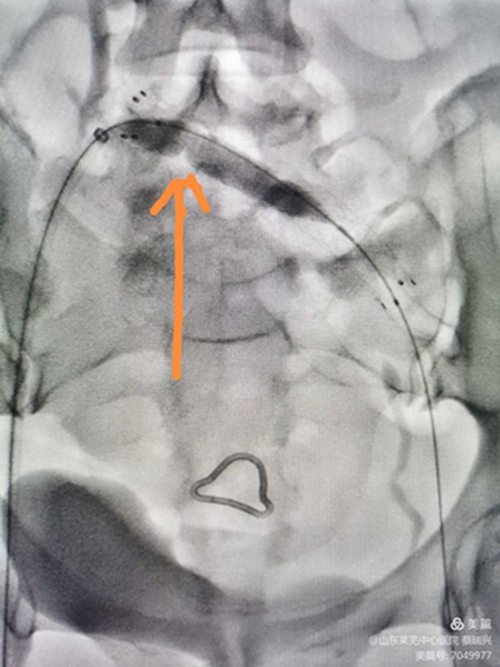

支架置入后,行后擴(kuò)張,閉塞部位球囊成形,有"腰征",且擴(kuò)張阻力大,說明是閉塞,且已閉塞很長時(shí)間。(如是壓迫或新閉塞,支架自行成形好,一般不用后擴(kuò)。)

后擴(kuò)滿意